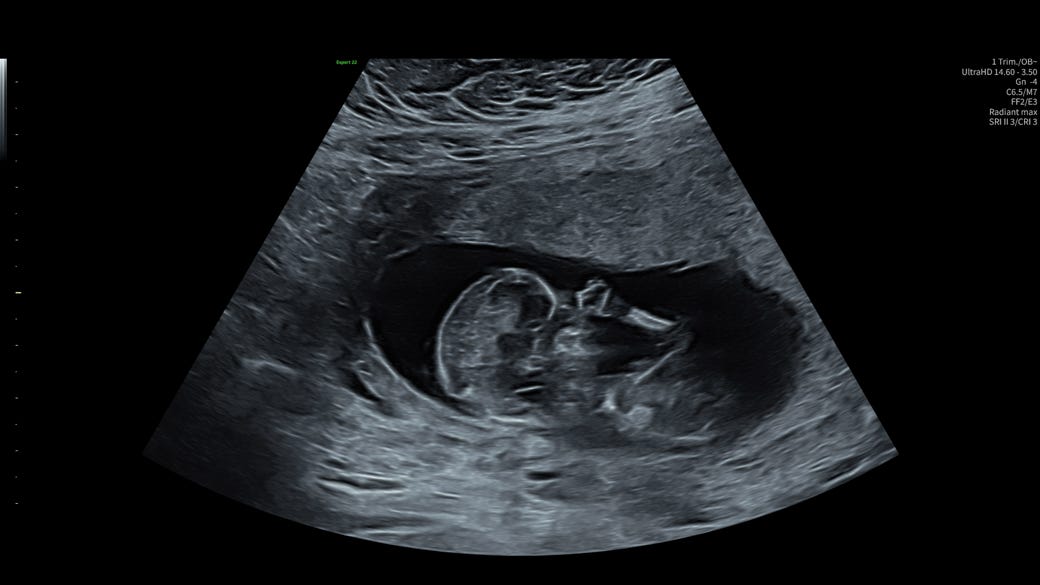

For the last two years, those physical photographs have sat in a drawer of my desk, unexamined. That changed recently. A few months ago, I fell pregnant. At ten weeks, I went into the doctor’s office for the second ultrasound. I had seen on the internet already the illustrations of what a ten-week-old foetus looks like, more alien or sea creature than humanoid. At ten weeks it had only recently lost its tail, ears were just beginning to form. On the screen I could see two white lobes, tiny, one for a future-body, and one for a future-head. I was handed the print-out photograph of the sonogram, and took it home, stuck it on the fridge between the pharmacy’s pollen count calendar and a friend’s illustration of Walter Benjamin in a Where’s Wally? hat. Now I had a photograph, a physical thing I could hold, of my future-human.

Four weeks later, I had another ultrasound, this one with high-tech equipment in a doctor’s office on Kurfürstendamm, one of Berlin’s ritziest and most storied thoroughfares. Suddenly the foetus looked indisputably human. It had feet and hands, and a sex. Her nose was one of the first things I noticed on the screen—reminding me even in hazy black and white shadow of my grandmother’s nose. I had, that day on Kurfürstendamm, the distinct sense that time was bending. As I looked at the images of the baby on the screen, two things occurred to me: one day that tiny foetus in black and white would become an old woman; and that I was carrying the future inside me. In my body the eggs in my baby’s ovaries were forming, potential grandchildren. And part of me too, I suddenly realised, was formed in my own grandmother’s womb in 1958 when she was pregnant with my mother. The lineage of generations suddenly felt of phenomenal significance. I found myself, that day after the ultrasound, taking the old photographs out and splaying them across the dining table. I picked out those showing my grandmother, my mother, and myself, all as children. As though in studying three generations of faces I could pick out the first hint of the face my future child would carry.

The thing was, I had also seen her move. I had received a new sonogram photograph of the foetus during that fluttery, tumbling week, at the monthly ultrasound, I had seen her tiny feet curled up beneath her and rubbing together like her father as he falls asleep. But after a week, the reassurance of the image no longer held the same power. I Googled foetal heartbeat monitors and whether or not one could buy an at-home ultrasound kit in Germany, knowing to do so would be to invite a level of madness into our lives that couldn’t really be withstood. I searched for the kind of extortionate businesses an American friend had told me they’d visited in Texas, where you can pay for a medically unnecessary ultrasound in order to get a series of good photographs for your friends, or a recording of the foetal heartbeat placed inside a teddy bear. I thought these clinics were grotesque, but if there’d been one available in Berlin, I would have booked an appointment in a heartbeat.

One morning, talking to my mother back in Sydney about some of these anxieties, she said, ‘your problem is that you’ve seen too much.’ When she was pregnant with me, my mother said, she only had the one ultrasound, and it wasn’t very clear or exact. At all other times she just trusted that I was safe inside her stomach, doing okay. It was a whole different ballpark for me—I had been fed images from the opening weeks of the pregnancy, and got them on a monthly basis, sometimes even more frequently than that. I had so many sonogram prints stuck to the fridge between the pollen calendar and Walter Benjamin as Wally. I was used to getting regular updates from the transducer, pinned my sense of comfort and reassurance to the production of those black and white images. It’s the photographs that were the problem, my mother thought: too much knowledge a dangerous thing.

During this period, I created a new ‘album’ on my phone titled ‘Baby’. In it are included photos of the foetus when she was the tiniest smudge in my belly, through pictures of her heart and brain and umbilical cord at fourteen weeks gestation, and recent pictures of her now, in proportion, accumulating centimetres and grams. I have pictures of her jumping and rubbing her nose and touching her own feet. There are over thirty images in the album, all of a child that has not yet been born, and most of which don’t exist as physical images stuck to the fridge—the majority have been delivered to us via QR code and downloaded in bulk to my phone. The album on my phone is an archive of the future—it delivers me images of a life before life has yet begun. It is a kind of anti-elegy. It doesn’t restore to life that which is gone, instead the loss it anticipates is, in fact, life.

I find the existence of these images uncanny, unsettling—a part of me thinks that they should not be. But I look at them all the time. I have looked at them while writing this piece, for reassurance, for some acknowledgment that she’s there. When she is an adult, there will exist an archive of images, all digitised, documenting the development of her image from the eighth week of gestation. She will be born one hundred years after my grandmother, of whose childhood I have just a single image.

While writing this piece, I went for the second round of prenatal diagnostic screening. This time we were going to check for any anomalies in the baby’s anatomy. I lay back on the medical table with my husband sitting in a chair beside me, the screen enormous and hovering above us. There she was. She was bent-double, her feet paddling over her head, and she was hiding, the doctor said, behind my stomach. It was difficult for him to get a good image.

One of the big highlights of the experience is the moment when the doctor pushes a button and you enter a 3D rendering of the womb, all orange and beige. Friends had shown us their own versions of these eerie images: scrunched-up faces, thumb-sucking, taking a drink of amniotic fluid. Only, when the doctor pressed the button, we couldn’t see her. Or rather, what we could see were two little knees, and two little forearms, held straight up over her face and obscuring it. I would prefer not to, said my husband. Out on Kurfürstendamm among the designer storefronts and linden trees, this seemed, we said, like a good sign. An early refusal of the camera, a refusal to let us ‘know’ any more than we need to know for now.